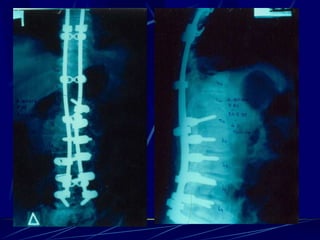

Post-operative infections